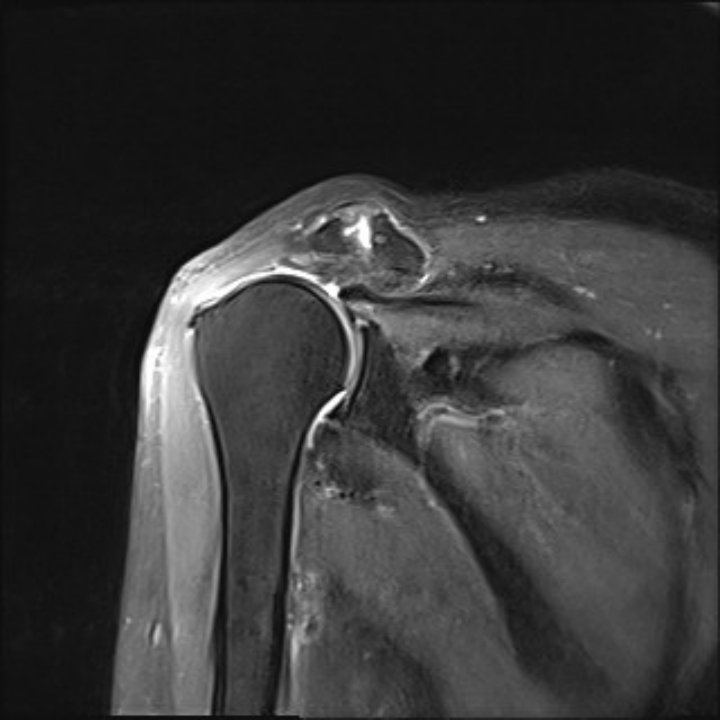

更糟糕的是,结合磁共振结果综合分析,金奶奶的肩袖撕裂程度相当严重,并且由于病情拖延太久,如今撕裂的肩袖巨大,肌肉脂肪浸润严重,属于巨大不可修复撕裂。

▲术前MRI,可以看到肩袖撕裂巨大